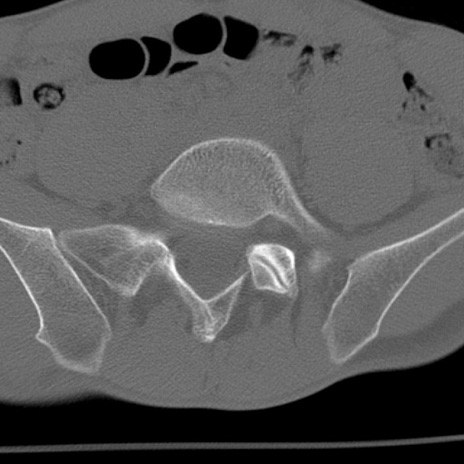

症例3 腰椎CT(横断像)

腰椎CT